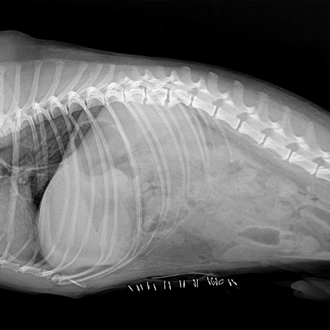

비뇨기계 수술

배뇨 곤란, 혈뇨, 결석 등 비뇨기 문제는 통증뿐 아니라 신장 기능에도 영향을 줄 수 있습니다.

원인을 확인한 뒤 아이 상태에 맞는 치료를 진행합니다.